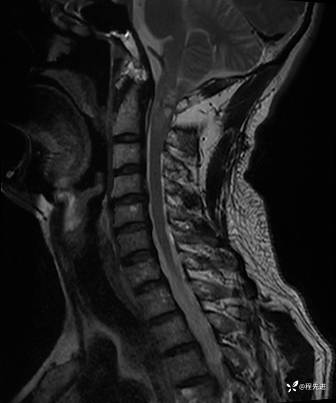

MRI平扫+增强:

T1增强: